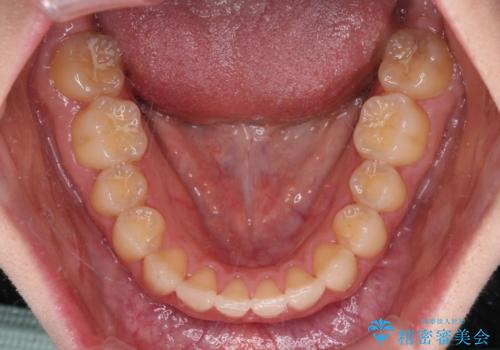

上顎のみの抜歯矯正 前歯のデコボコを改善する

奥歯の咬み合わせがなかなか定まらず、スペースが閉じるまでに時間がかかりましたが、最終的には正中を合わせることもできました。